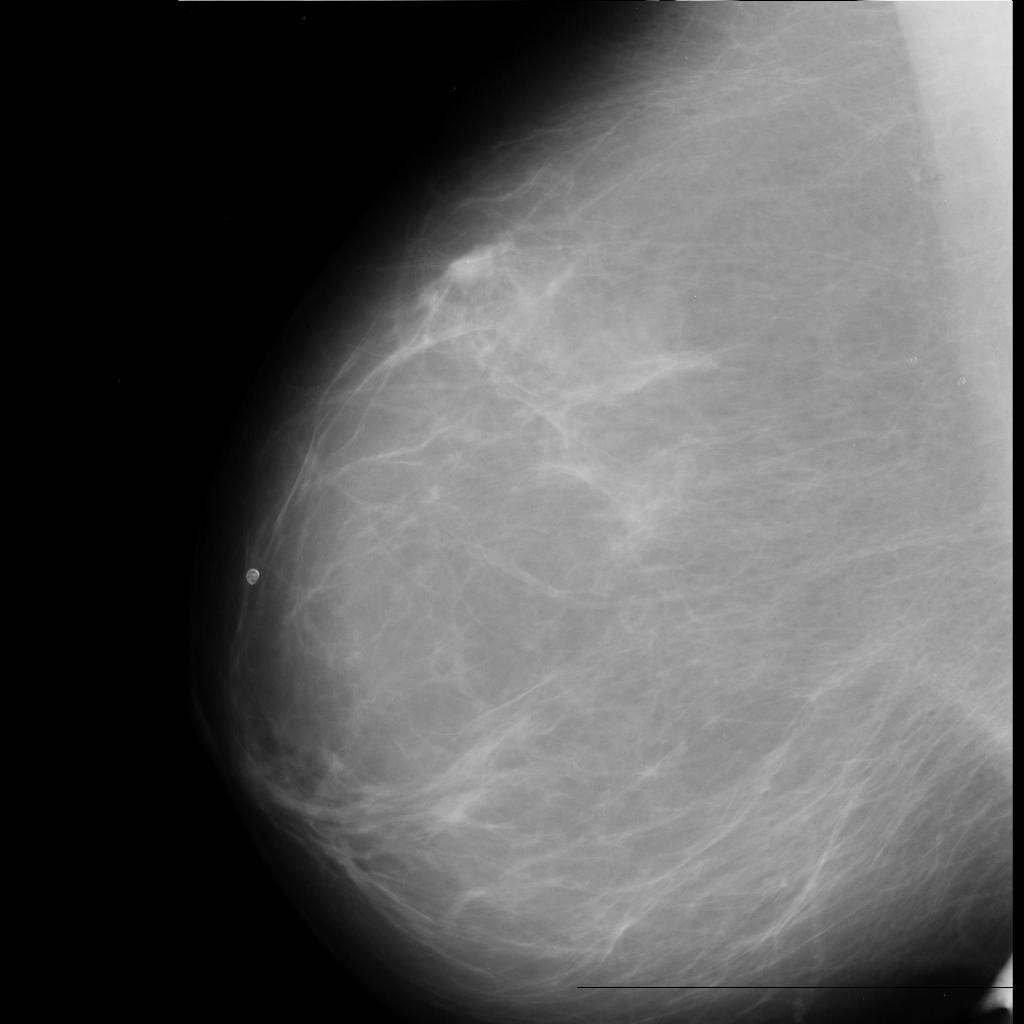

benign

malignant